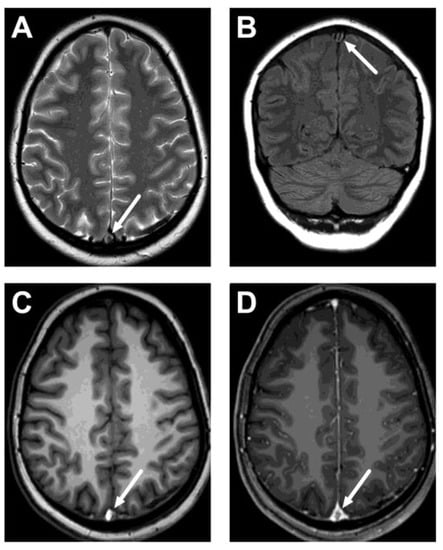

Figure 1.

True positive cases of cerebral venous sinus thrombosis. Axial (top row) and sagittal (bottom row) images of post-gadolinium T1-weighted 3D MRI images of five patients: a 26-year-old female (A), a 33-year-old female (B), a 21-year-old female (C), a 27-year-old female (D), and a 16-year-old male (E). Thrombosis is seen as a hypointense filling defect against the high signal from the gadolinium-based contrast agent in the venous sinuses, usually in the transverse sinuses (arrows) and the superior sagittal sinus (dotted arrows).